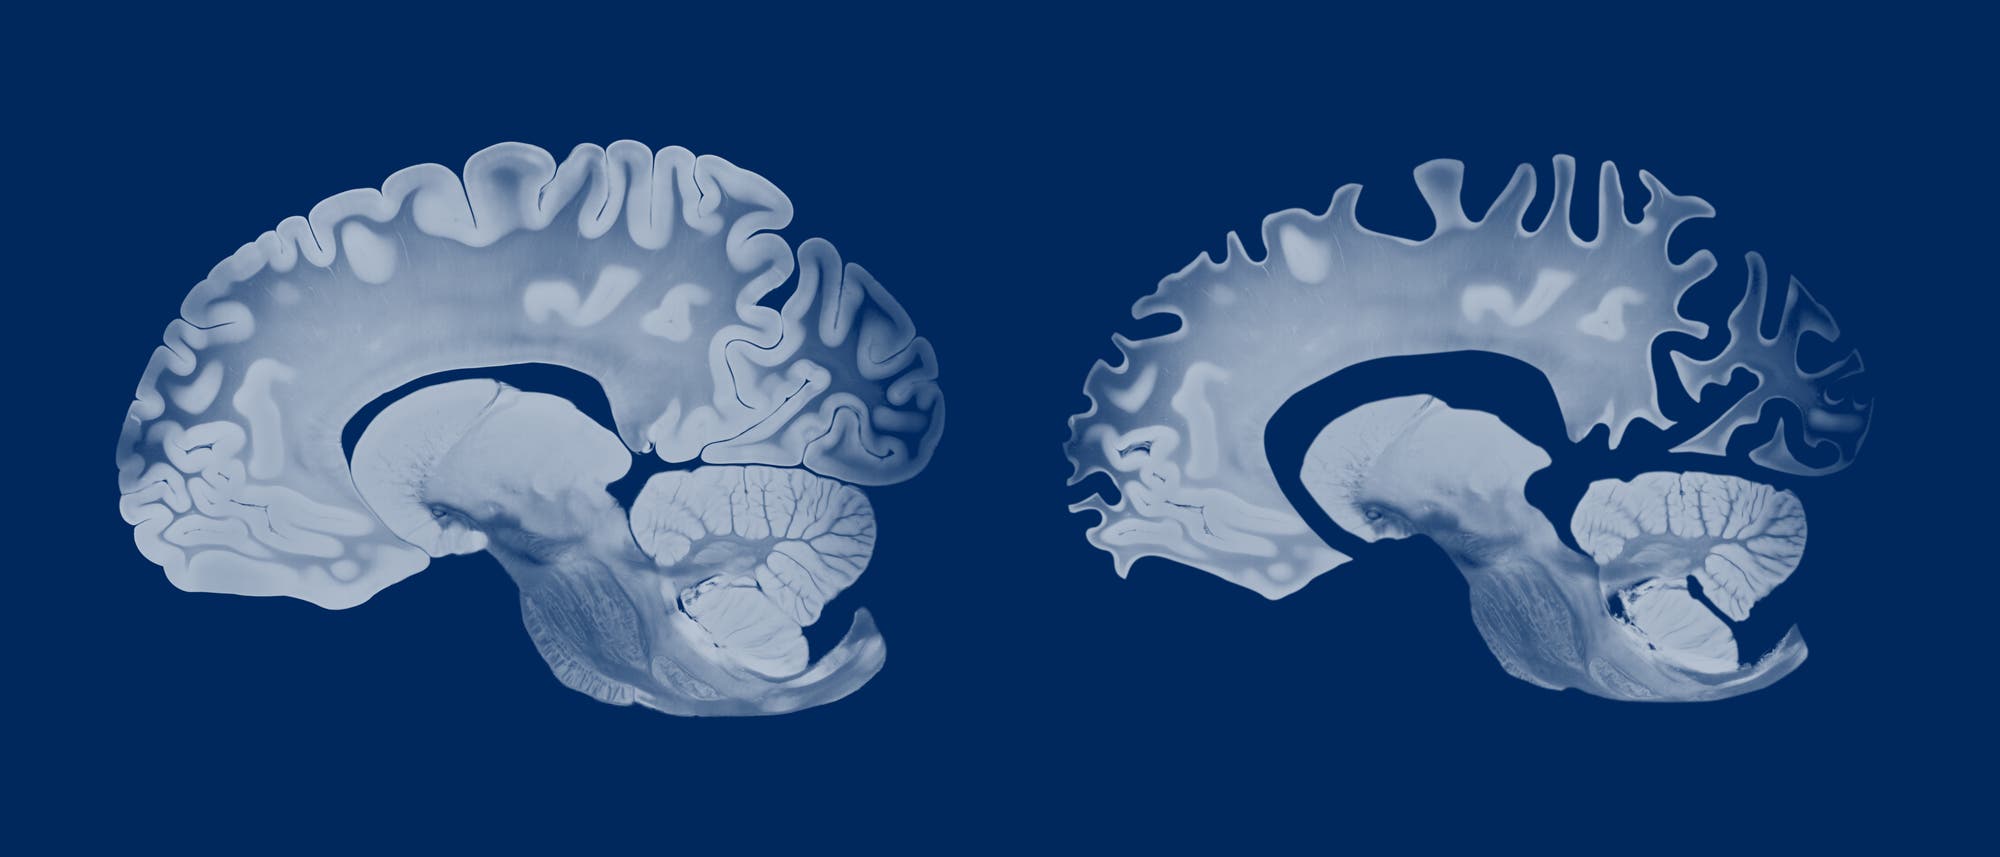

Trotz höheren Alzheimerrisikos: Frauenhirne schrumpfen im Alter langsamer

Im Alter schrumpft das Gehirn von Männern in vielen Bereichen stärker als das von Frauen. Zu dem Ergebnis kommt ein Team um Anne Ravndal von der Universität Oslo. Die Fachleute hatten mehr als 12 500 MRT-Aufnahmen von 4726 Versuchspersonen ausgewertet und beobachtet, wie sich die Hirnstruktur im Lauf der Zeit veränderte.

Bei Männern dünnte im Alter die Hirnrinde in manchen Bereichen stärker aus als bei Frauen – darunter im Sehzentrum am Hinterkopf sowie in der parahippocampalen Region, die bei der räumlichen Orientierung hilft. Am deutlichsten erkennbar war der Unterschied im Postzentralkortex, einem Areal, das haptische Sinneseindrücke verarbeitet.